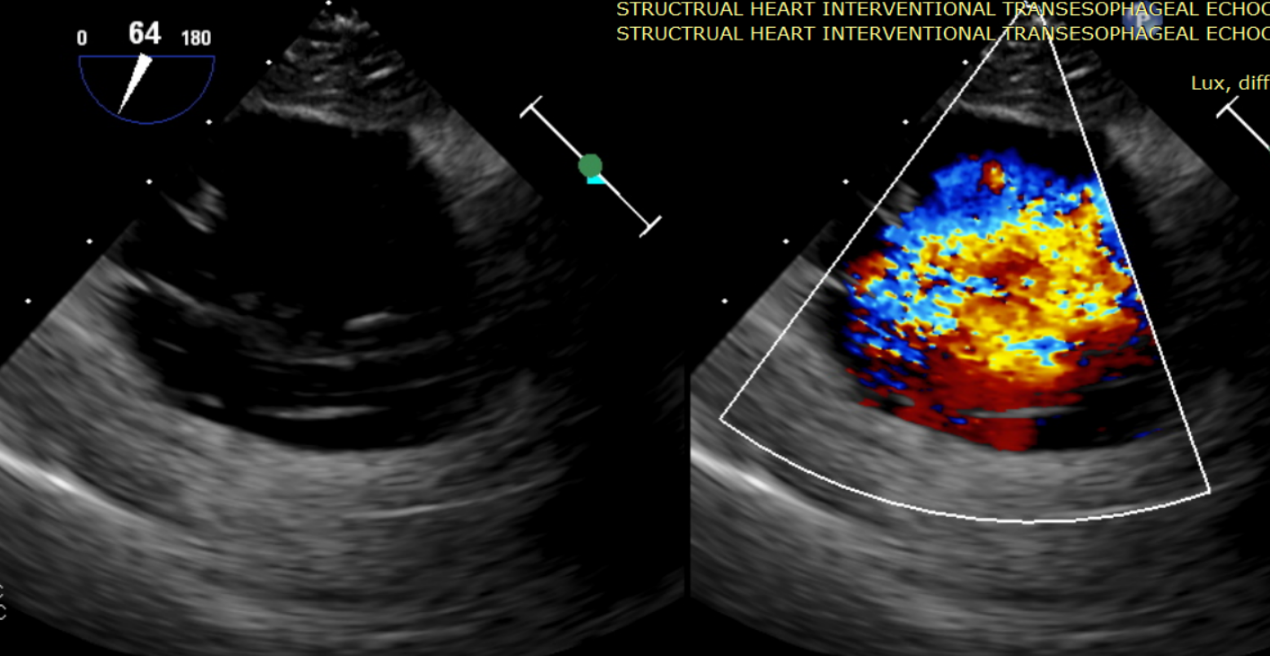

術中輸送器在超聲引導下調整位置